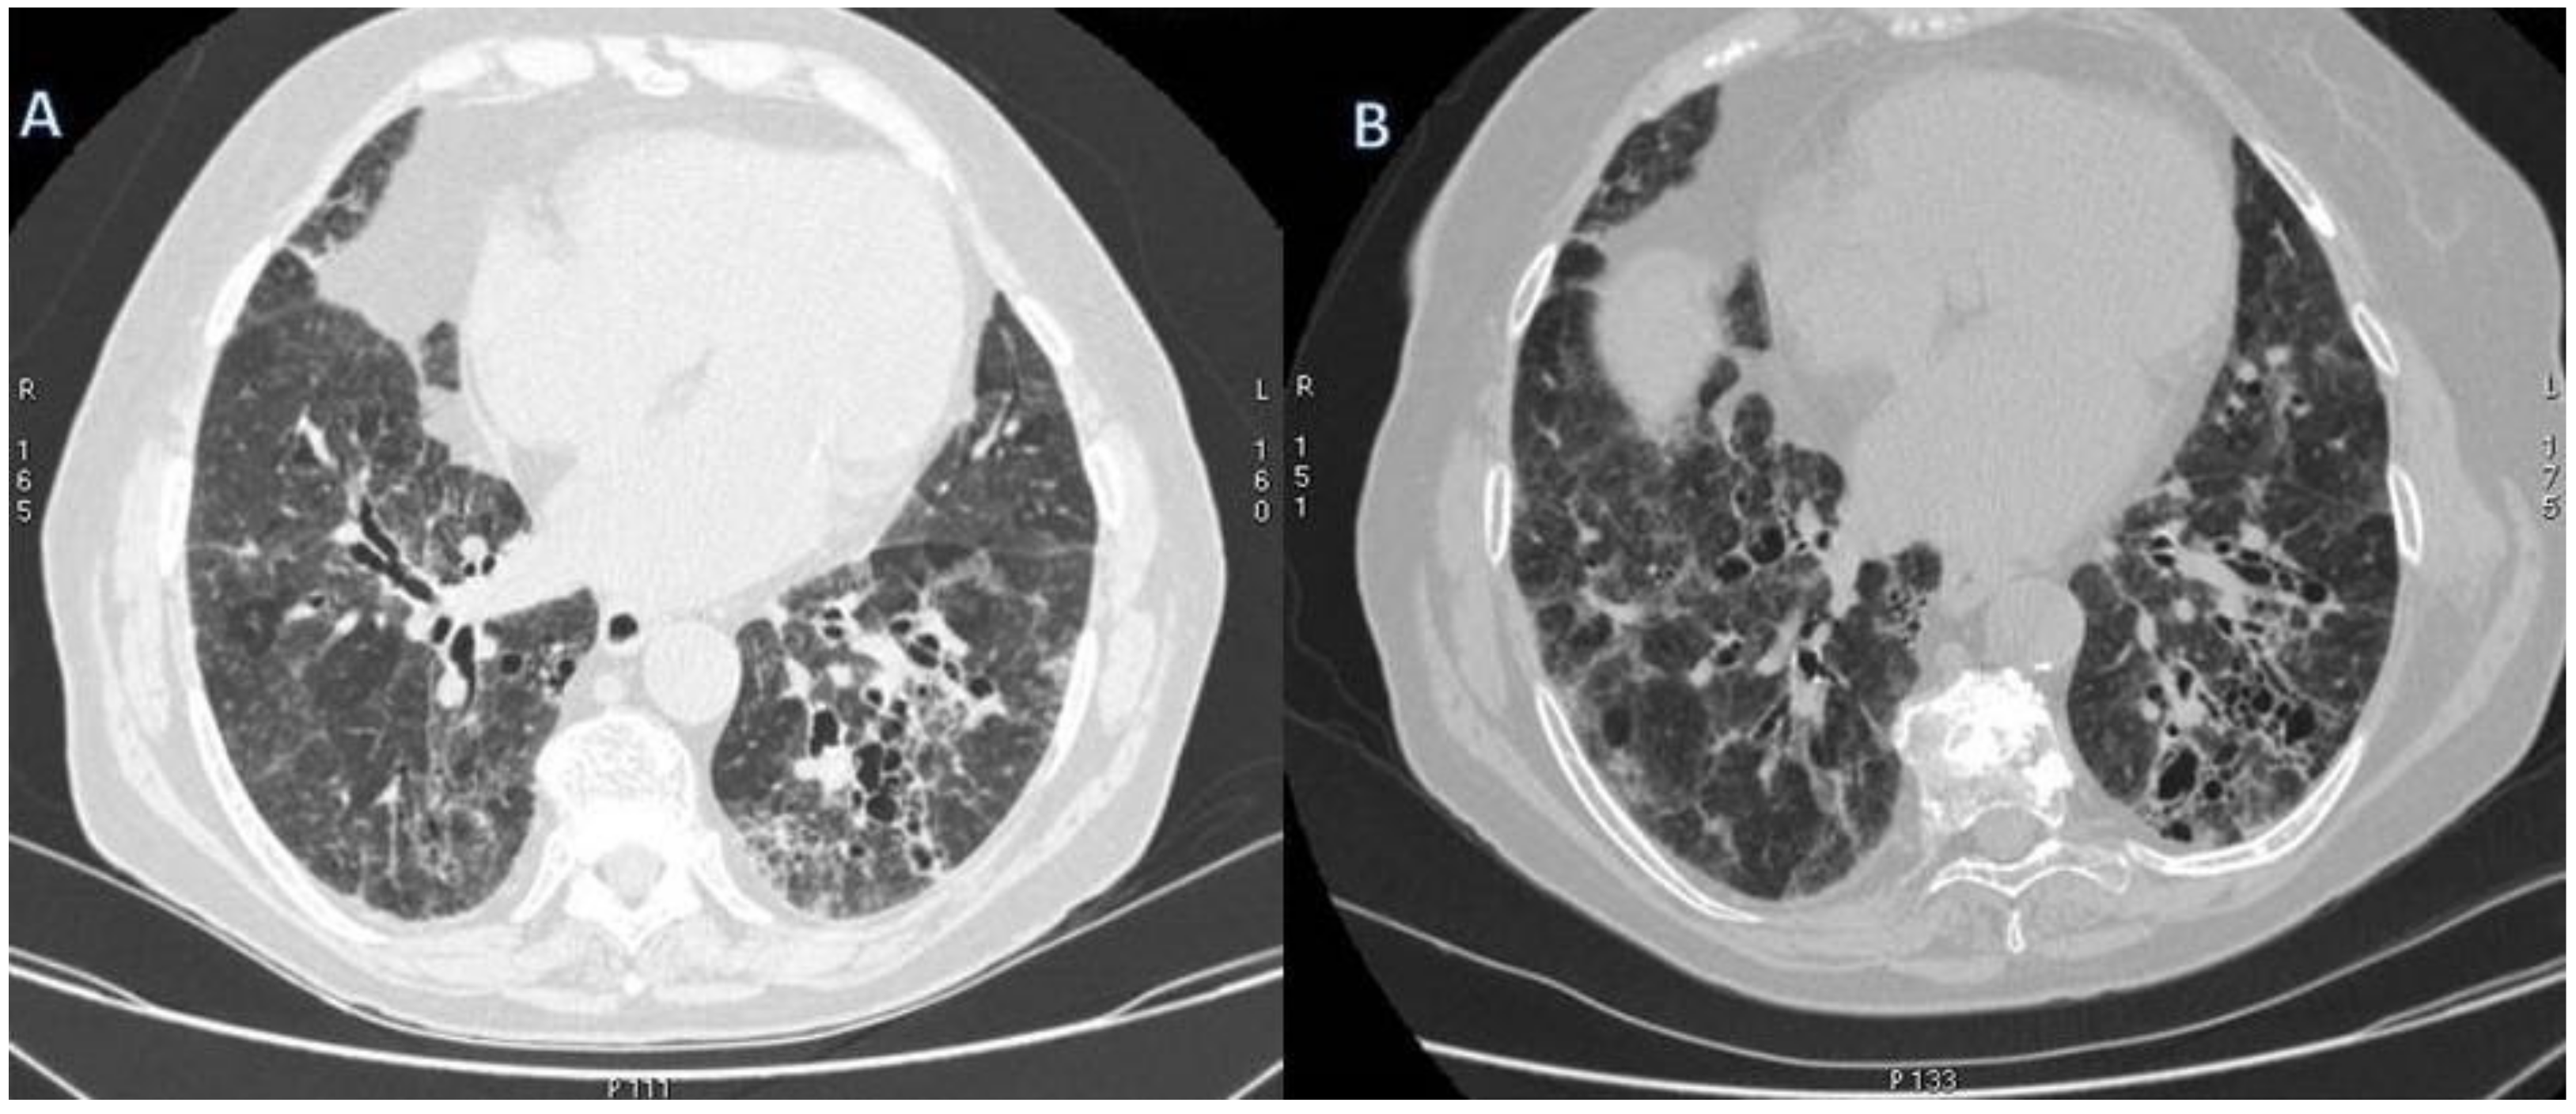

2.5. Eosinophilic Granulomatosis with Polyangiitis (EGPA-Churg-Strauss)

| EGPA | Migrant GGOs, transient consolidation, irregular bronchial wall thickening, small nodules with peribronchial and centrilobular distribution, pleural effusion. |